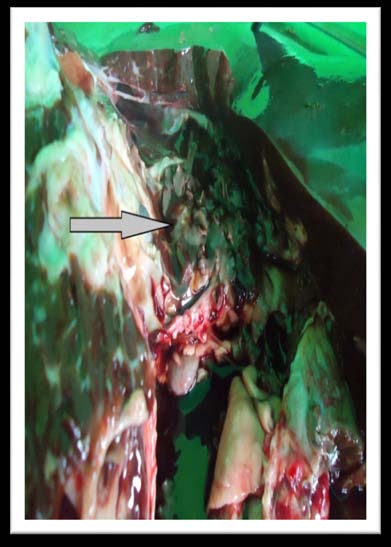

Worms were recovered from infected livers by squeezing them manually to macerate the parenchyma and the flukes were carefully removed and placed in petridish containing 0.15M Dubecco's PBS buffer (pH 7.3) for initial washing. The flukes were stored in collection vials containing PBS and were transported to the laboratory of Department of Zoology, University of Kashmir, Srinagar. Fasciolids were identified primarily on differences in body shape and size of the adults, with the smaller F. hepatica exhibiting wide and defined shoulders compared to the slender F. gigantica having less defined shoulders and shorter cephalic cones (Soulsby, 1986). For permanent slide preparation flukes were rapidly killed in 70% ethyl alcohol to avoid shrinkage. The flukes were then transferred to vials containing 6-10% formalin for preservation. Flukes were stained with Borax Carmine, dehydrated in ascending grades of ethanol, cleared in Xylene and mounted in Balsam Canada and viewed under monocular light microscope.

Of the total 192 affected livers by fasciolosis, 149 (77.60%), 24 (12.5%) and 19 (9.89%) respectively showed Fasciola gigantica, Fasciola hepatica and mixed infection (Fasciola hepatica and Fasciola gigantica).